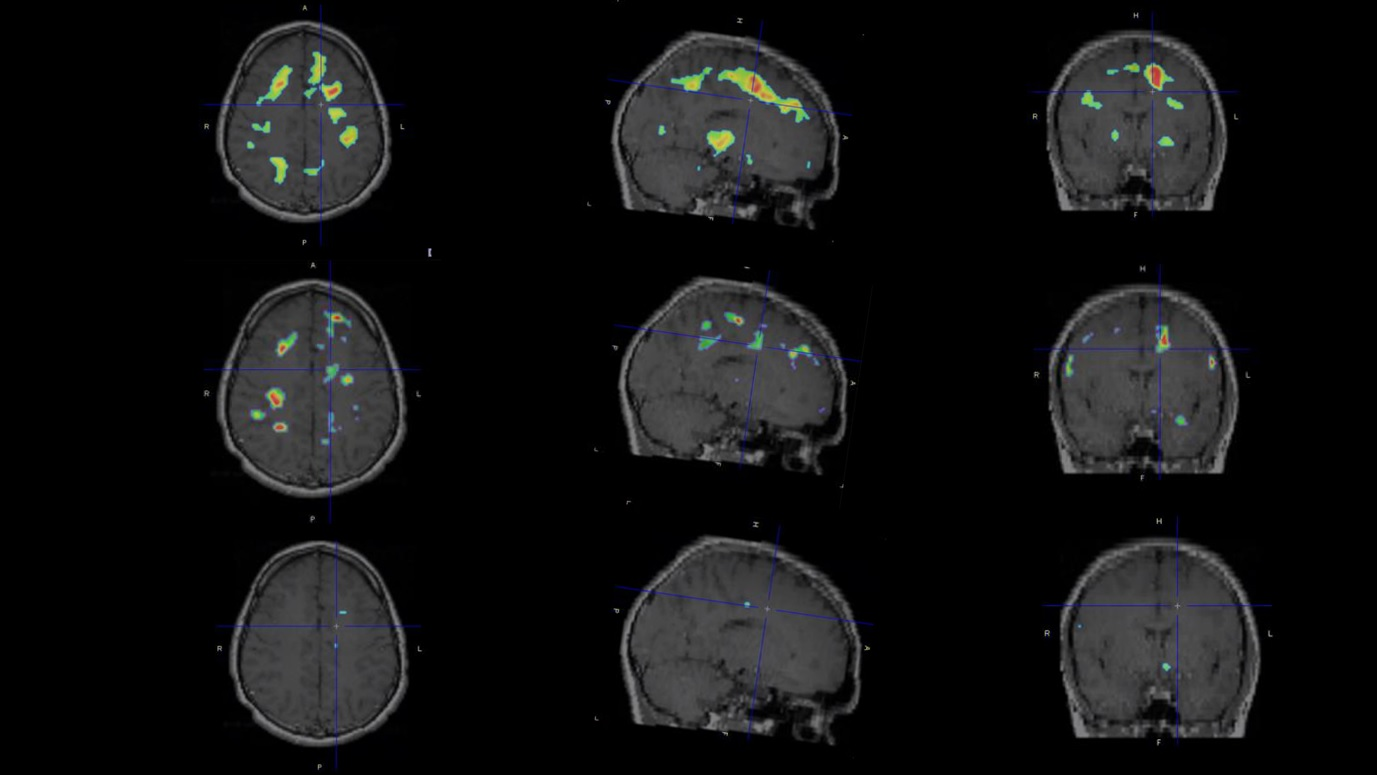

In addition, F-18 3F4AP generated a high signal in the right frontal cortex of a monkey that the researchers later learned had sustained a minor brain injury several years before being transferred to them.